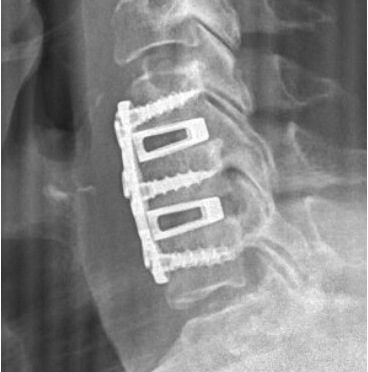

X-ray image of a spine with spinal hardware implant.

• Anterior Cervical Discectomy and Fusion (ACDF)

• Cervical disc replacement (for select patients)

• Posterior Cervical Foraminotomy